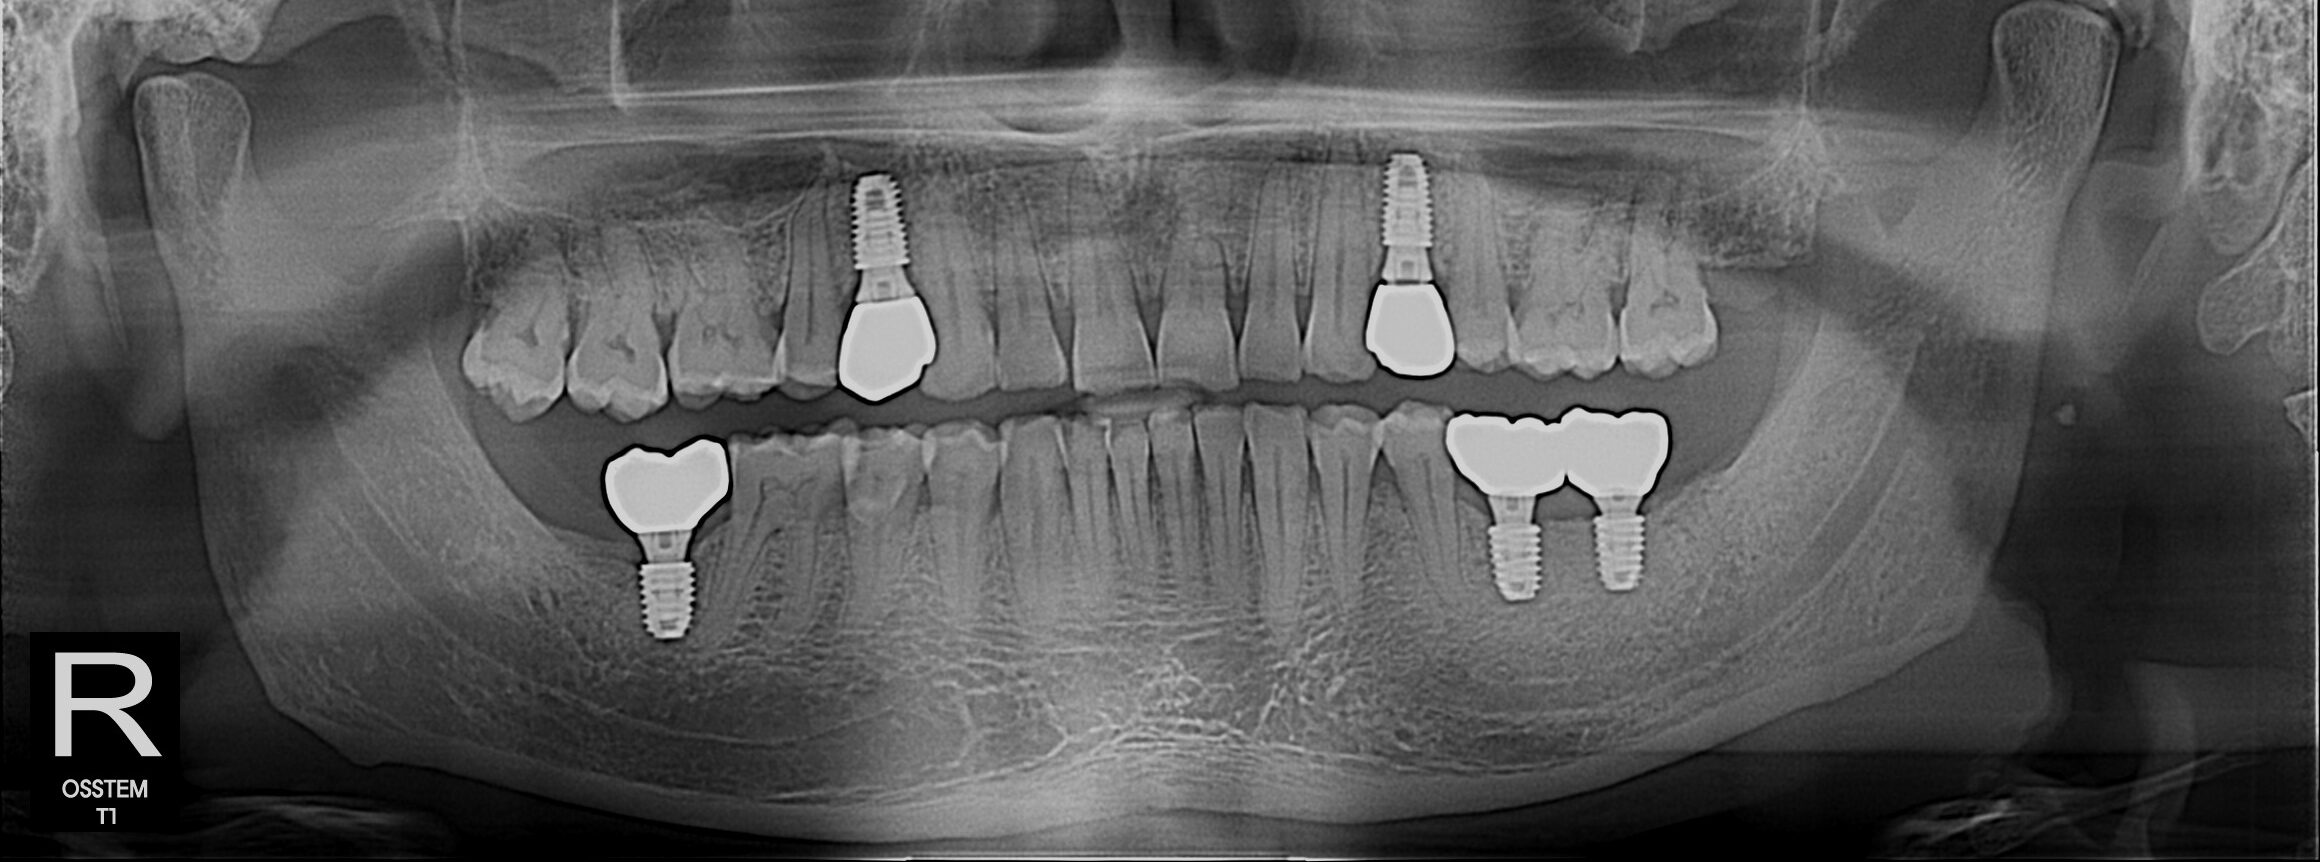

Implant Gallery